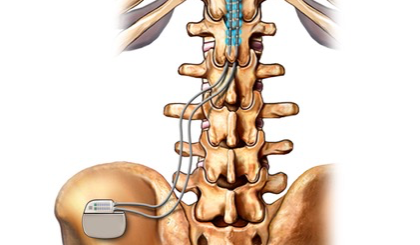

- Neuromodulation